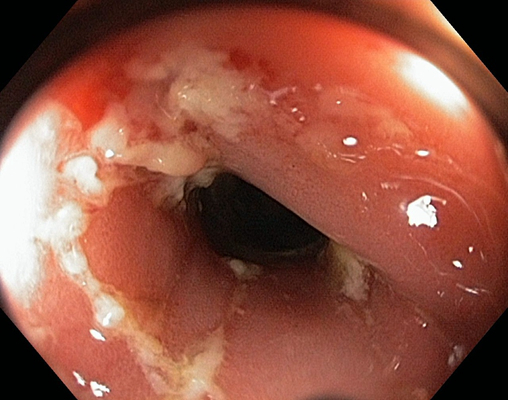

肛門癌圖片

肛癌早期症狀